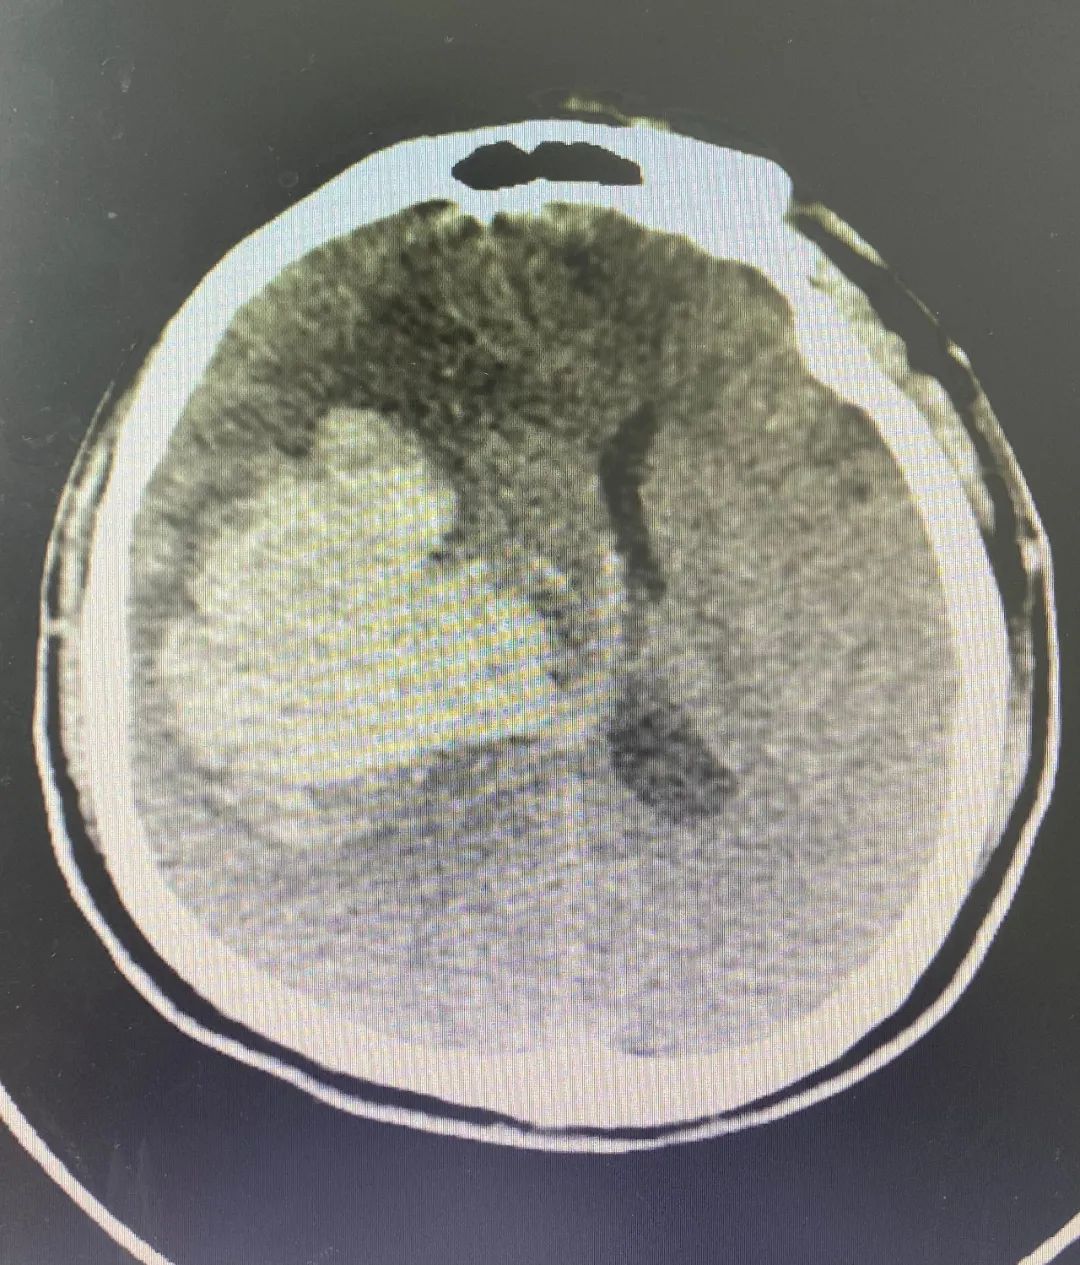

▲術(shù)前、術(shù)后CT對(duì)比

醫(yī)生告知家屬需要緊急進(jìn)行手術(shù),征得家屬同意后,隨即進(jìn)行術(shù)前準(zhǔn)備,并聯(lián)系福醫(yī)大附二院當(dāng)值專家徐朝陽主任,徐主任立即趕往我院協(xié)助開展全麻下“開顱右基底節(jié)血腫清除術(shù)+去骨瓣減壓術(shù)”,手術(shù)順利。

術(shù)后劉先生轉(zhuǎn)入ICU病房密切觀察,診斷其肺部并發(fā)癥嚴(yán)重,痰較多,在徐主任及我院神經(jīng)外科團(tuán)隊(duì)、ICU病房醫(yī)護(hù)人員等多方精心治療與照料下,病情好轉(zhuǎn)并從ICU轉(zhuǎn)入神經(jīng)外科病房接受進(jìn)一步治療。徐主任時(shí)常跟蹤病情和指導(dǎo)相關(guān)治療方案,目前患者病情趨于穩(wěn)定。劉先生及家屬非常慶幸在家門口就能享受優(yōu)質(zhì)的診療服務(wù),對(duì)我院神經(jīng)外科團(tuán)隊(duì)精心照顧與照護(hù)表示感激,并給予點(diǎn)贊。